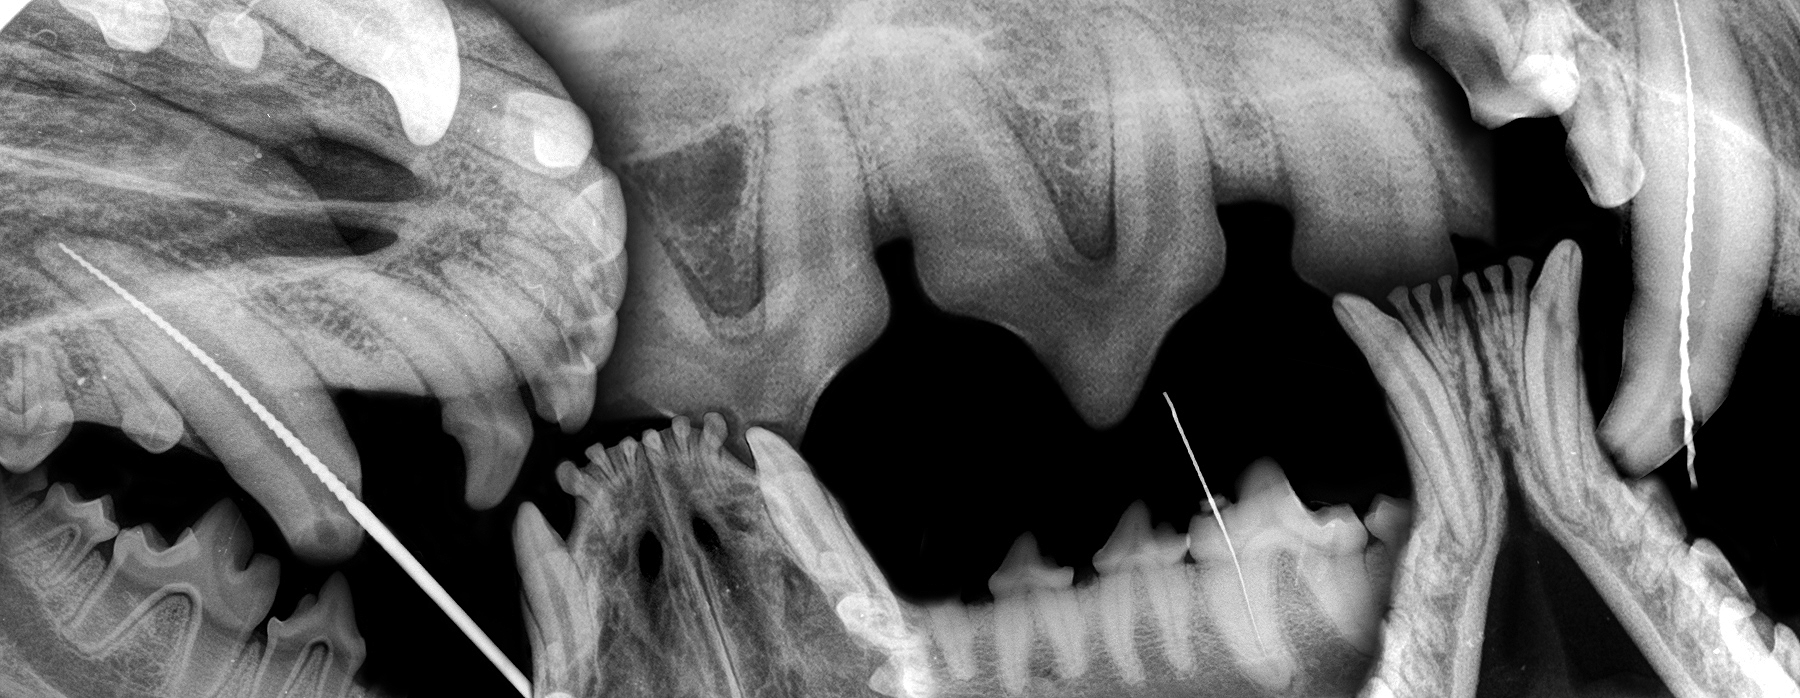

ZAHNÄRZTLICHE BILDGEBUNG

DIE ZAHNÄRZTLICHE RADIOLOGIE IST FÜR DIE ORDNUNGSGEMÄSSE PATIENTENVERSORGUNG VON ENTSCHEIDENDER BEDEUTUN